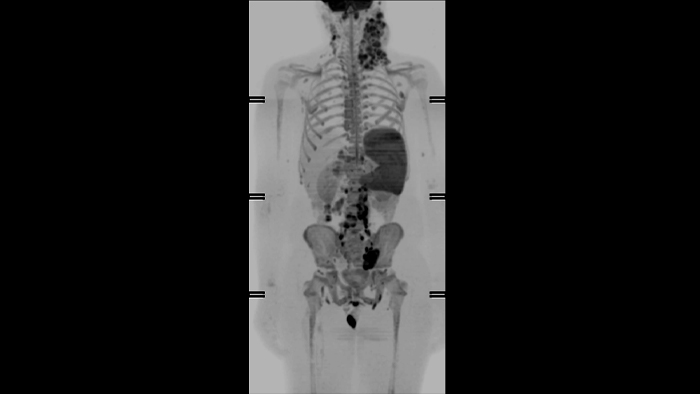

DWIBS

Clinical application

Whole Body  HeadNeck

Tokai University, Japan

2004